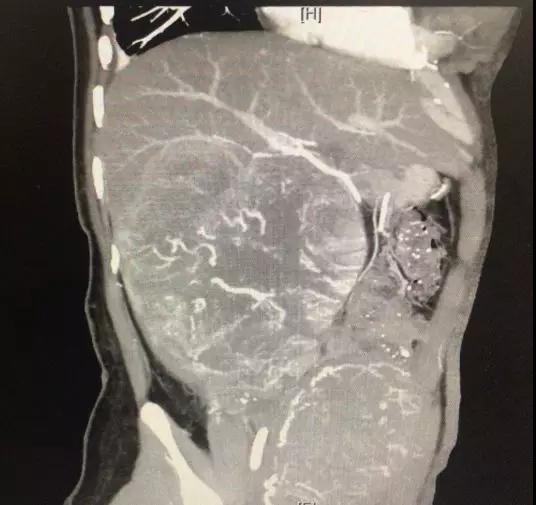

随着时间的推移,王莉背部的疼痛加重,右上腹还出现了一个“包”,摸上去硬硬的,伴有烧灼感,这个包块似乎在跟“孕肚”比赛谁长得快,在孕期36周彩超检查时,发现“包块”在王莉的肝肾之间,并且还不止一个“包块”,最大的有18×12厘米大,最小的也有3×4厘米,加上肝癌标志物甲胎指标非常高,可以基本确定肿瘤是恶性的。医院妇产科和肝胆外科专家经过全面评估后,决定尽快收治入院施行剖腹产,以保证准妈妈和胎儿的安全。

针对患者的复杂的病情,在充分的术前调理后,新桥医院肝胆外科郑璐副主任率团队,根据“包块”侵犯周围脏器的情况,术前引入当前国际最先进最新面世的混合现实(Mixed Reality,MR)技术,生成患者肝脏、肿瘤和大血管的全息模型,直观而全面的明确肿瘤与血管、脏器等详细信息,根据这些信息制定更完美的术中路径方案,让手术专家做到“心中有数”、“心中有路”,以最大限度降低手术风险,完成肿瘤切除。

在新桥医院肝胆外科的手术室内,郑璐副教授和他的团队,利用MR技术生成的患者全息模型,精准快速定位肿瘤组织,既保证肿瘤切除干净彻底,最大限度地保留了患者的功能性肝组织,又有效避免大血管、胆管、周围组织器官不受损伤。整个手术历时4小时,切除的“魔丸”重量比婴儿还重,足足有5.6斤重。术后当天,王莉的高烧就好转,术后一周各项生命体征平稳。